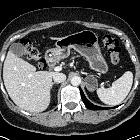

CT/MRI

A well defined saccular collection of fluid or gas that demonstrates communication with the gastric cavity (fills with iodinated oral contrast on CT).

In cross-sectional studies gastric diverticula can mimic a left adrenal mass. In fluoroscopic studies, they may mimic a gastric ulcer.